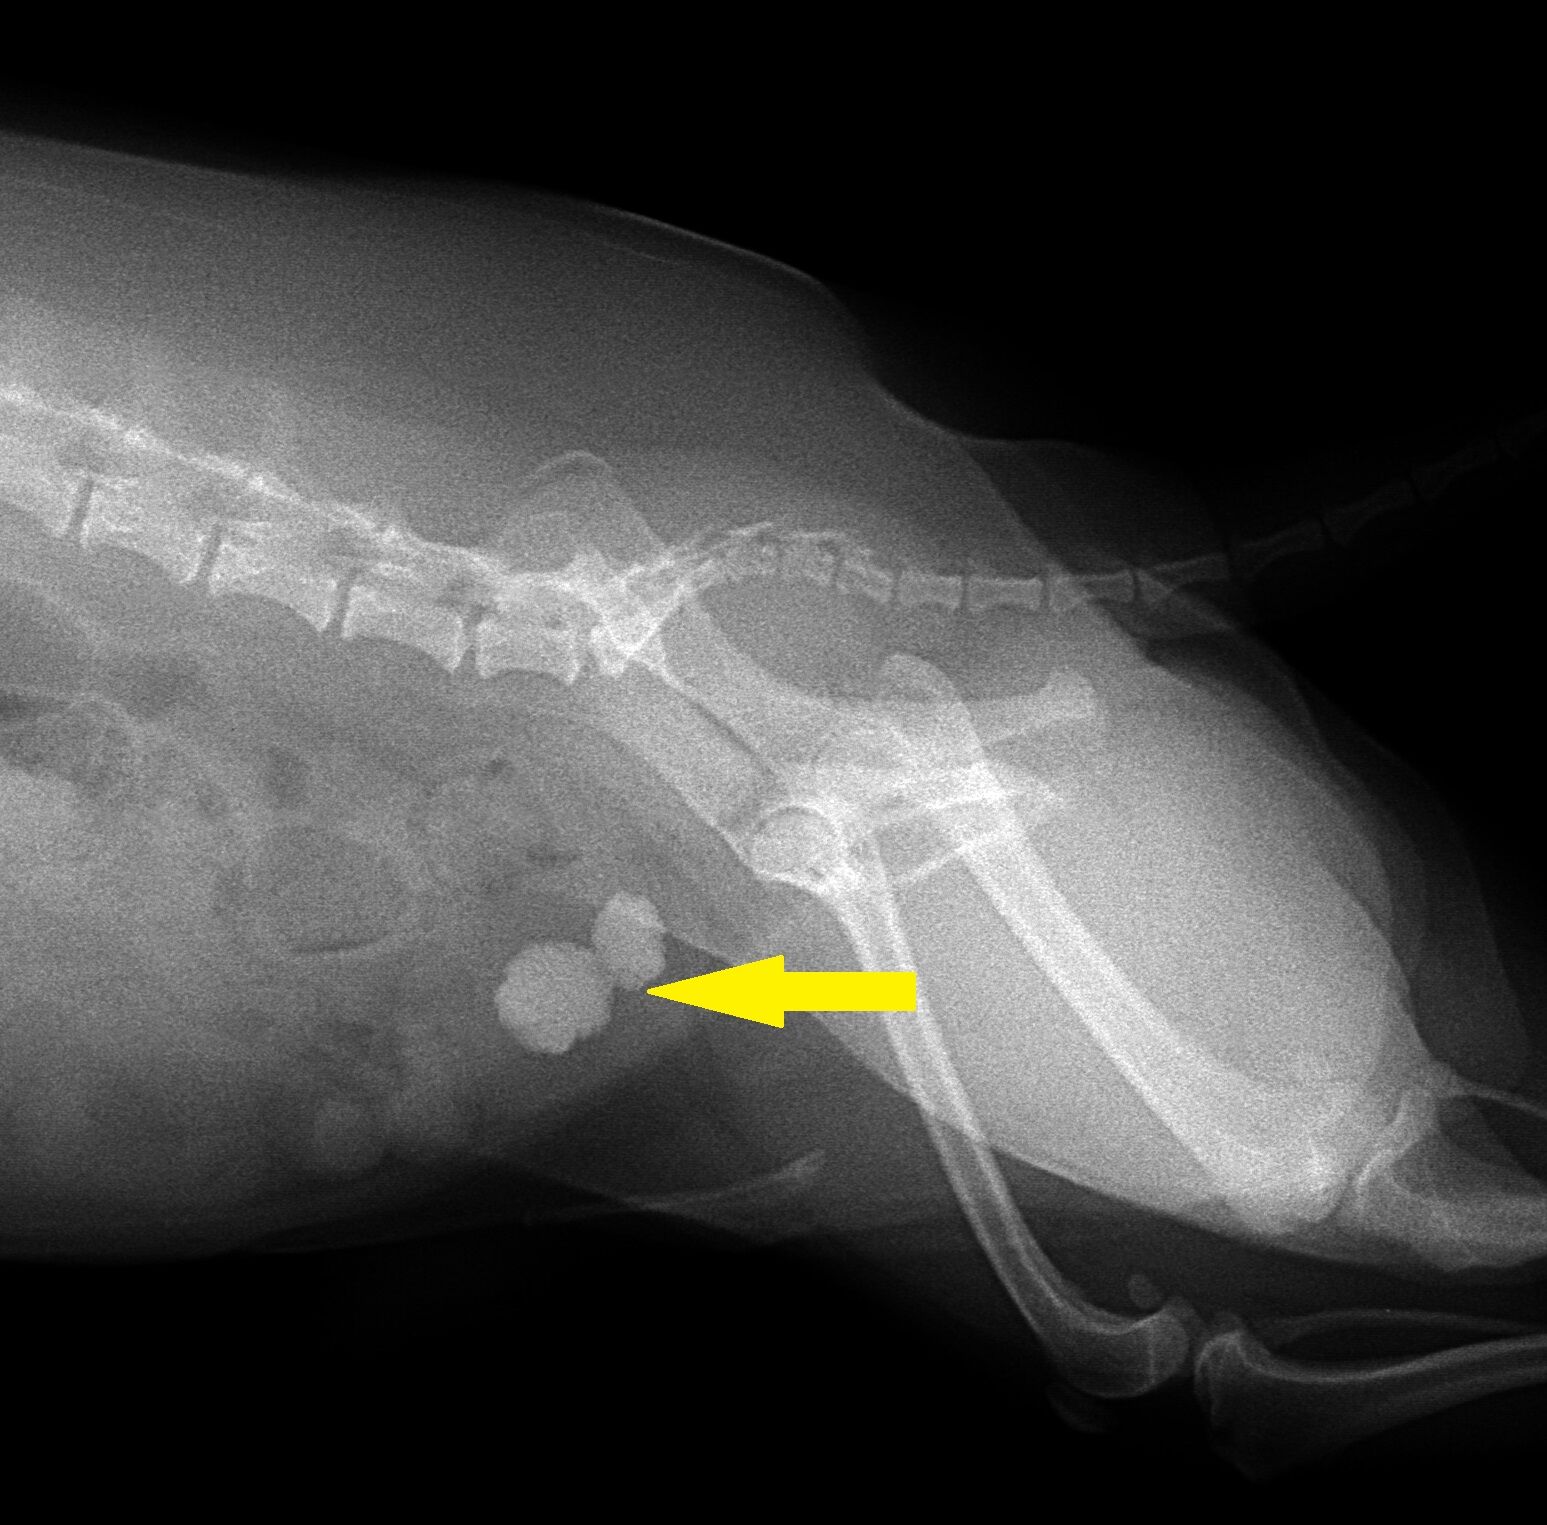

今回はワンちゃんの膀胱結石を取り除く手術について報告させて頂きます。8歳の男の子です。1年ほど前に血尿が出るということで来院されました。その時は尿中に結晶があり、それが原因で血尿が出ていました。その時点では膀胱結石は認められなかったので、内服と膀胱結石の予防用フードで完治しました。尿中の結晶は体質的に出ている可能性があったので、予防用フードを続けることを指示しておりました。しかしその後飼い主さんは来院されることはなく、次に来た時には尿が出にくくなった、とのことで約1年後に来院されました。レントゲンを撮ったところ、下のように膀胱結石が2個できていました。

矢印の丸い2つのものが膀胱結石です。これくらい大きくなってしまいますと手術で取り除いてしまうしかありません。手術して取り除いた結石が下の写真です。